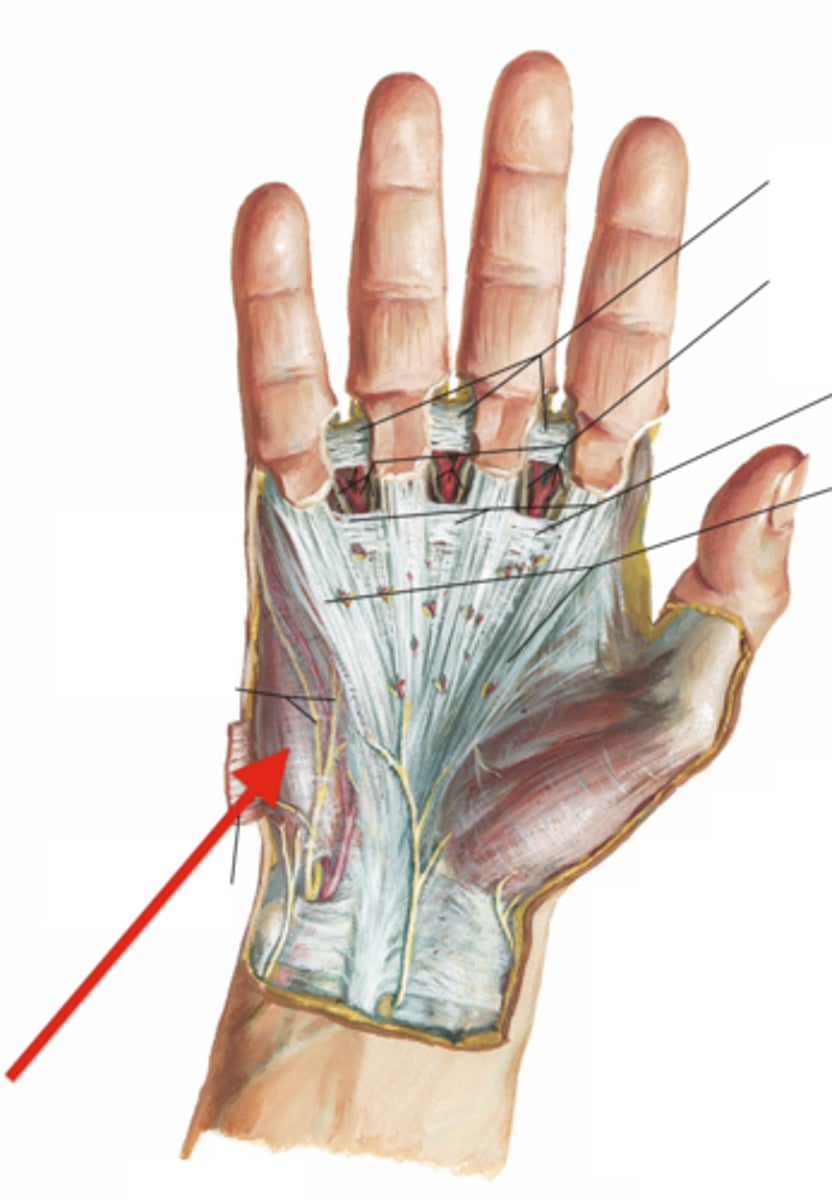

(Upper Limb Fascia:) Fascia of palmar region

(Fascia of palmar region:) Palmar Fascia

inferior continuation of the antebrachial fascia onto the hand

Contains: Palmar aponeurosis, Thenar fascia, Hypothenar fascia

(Fascia of palmar region's Palmar Fascia:) Palmar aponeurosis

thick and strong, overlies the central compartment of the palm. Continuous superiorly with the flexor retinaculum and palmaris longus tendon (when present) and forms central compartment of hand

(Fascia of palmar region's Palmar Fascia:) Thenar fascia

forms lateral compartment of hand, containing the thenar muscles at the base of the thumb

(Fascia of palmar region's Palmar Fascia:) Hypothenar fascia

forms medial compartment of hand, containing the hypothenar muscles proximal to the base of the 5th finger

(Antebrachial fascia:) Transverse bands

-Flexor retinaculum (transverse carpal ligament)

-Palmar carpal ligament

(Antebrachial fascia's Transverse bands:) Flexor retinaculum (transverse carpal ligament)

forms the roof of the carpal tunnel, which contains flexor tendons and the median nerve

(Antebrachial fascia's Transverse bands:) Palmar carpal ligament:

in the anterior region superficial to the flexor retinaculum, and continuous with the extensor retinaculum in the posterior region